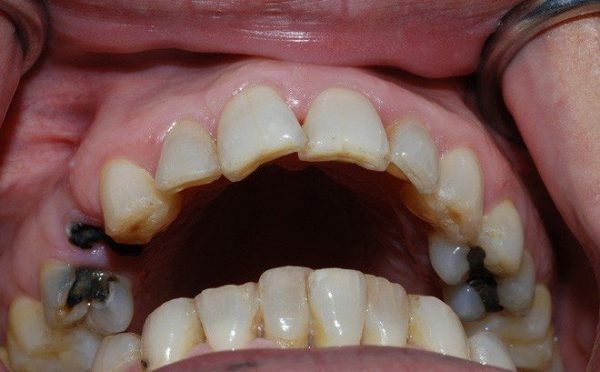

Phá hủy tính thẩm mỹ và rào cản tâm lý

Nụ cười là “vũ khí” quan trọng trong giao tiếp, nhưng sâu răng đen lại trực tiếp tước đi điều đó:

- Hàm răng “mất điểm”: Những lỗ hổng đen sì, sứt mẻ nằm ngay vị trí răng cửa hoặc mặt nhai khiến hàm răng trông thiếu sạch sẽ và “khó coi”.

- Tự ti trong giao tiếp: Người bệnh thường có xu hướng che miệng khi cười hoặc ngại nói chuyện, tạo rào cản lớn trong công việc và cuộc sống. Với các trường hợp này, phương pháp bọc răng sứ là cứu cánh giúp tái tạo nụ cười trắng sáng và tự tin hơn.